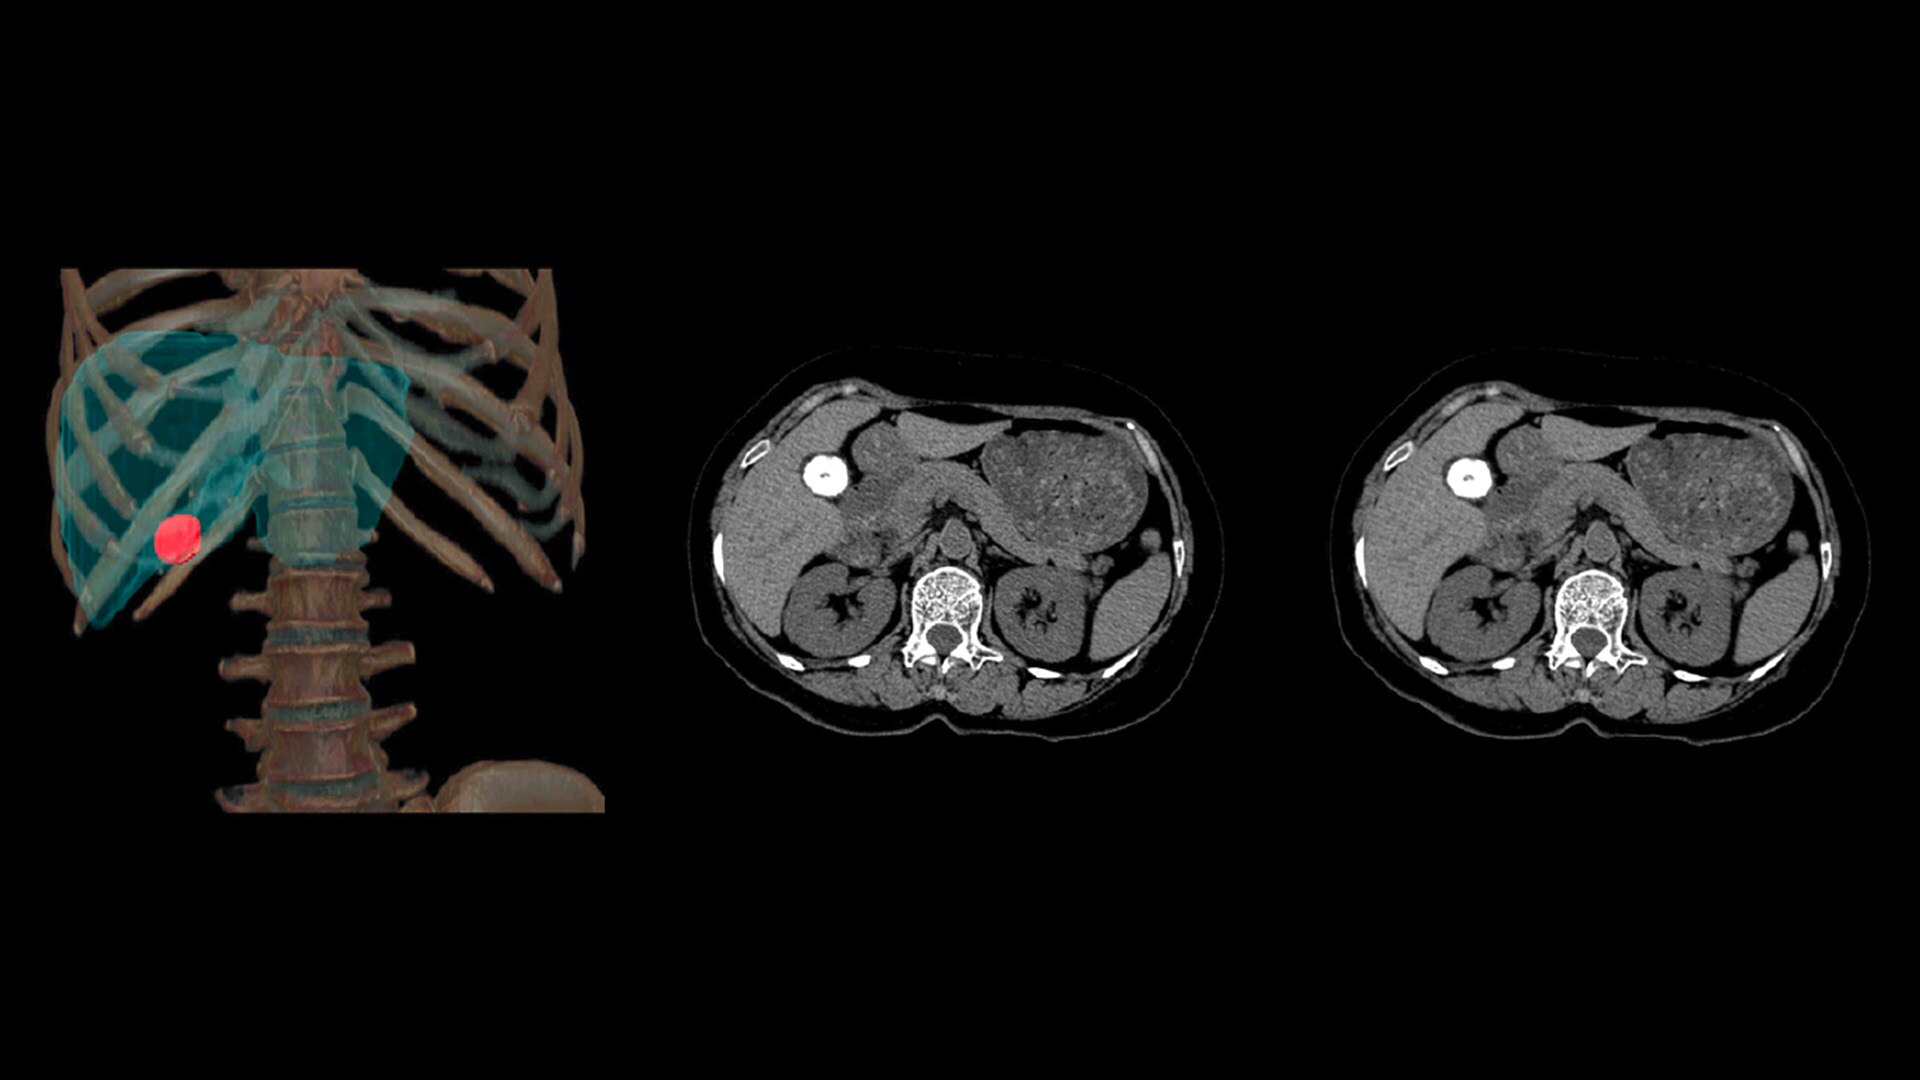

At the heart of Revolution Advance is a high-performance, reliable imaging chain with 42 kW of generator power, a 3.5 MHU X-ray tube and integrated detectors that reduce signal-to-noise by 20%2. This is paired with our smart, dose-reducing reconstruction applications like ASiR2, which can provide up to 40% lower dose while maintaining high image quality2.

When it comes to imaging more challenging cases, such as neuro, oncology or pediatric patients, VISR3. (Volumetric Image Space Reconstruction) reduces noise without impacting image resolution. This means less dose for the patient while maintaining the high-image quality you need for more accurate diagnoses.